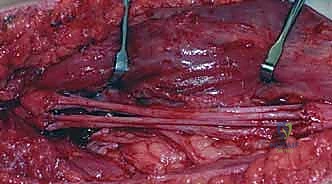

رابعاً: الإصلاح الجزئي وترقيع العصب (Split Repair & Nerve Grafting)

في بعض حالات "الإصابات المتصلة"، يجد الجراح أن جزءاً من الحزم العصبية داخل العصب سليم ويعمل، بينما جزء آخر تالف تماماً وتحول إلى ندبة ميتة.

* التقنية: يقوم الدكتور هطيف بفصل الحزم السليمة عن الحزم التالفة (Split). يترك الحزم السليمة لتقوم بوظيفتها، بينما يقوم باستئصال الجزء التالف من الحزم الأخرى.

* الترقيع: لتعويض الفجوة الناتجة عن استئصال الجزء التالف، يتم أخذ عصب حسي غير أساسي من المريض (غالباً العصب الربلي من الساق Sural Nerve) واستخدامه كـ "جسر" أو "رقعة" لتوصيل نهايات الحزم المقطوعة.